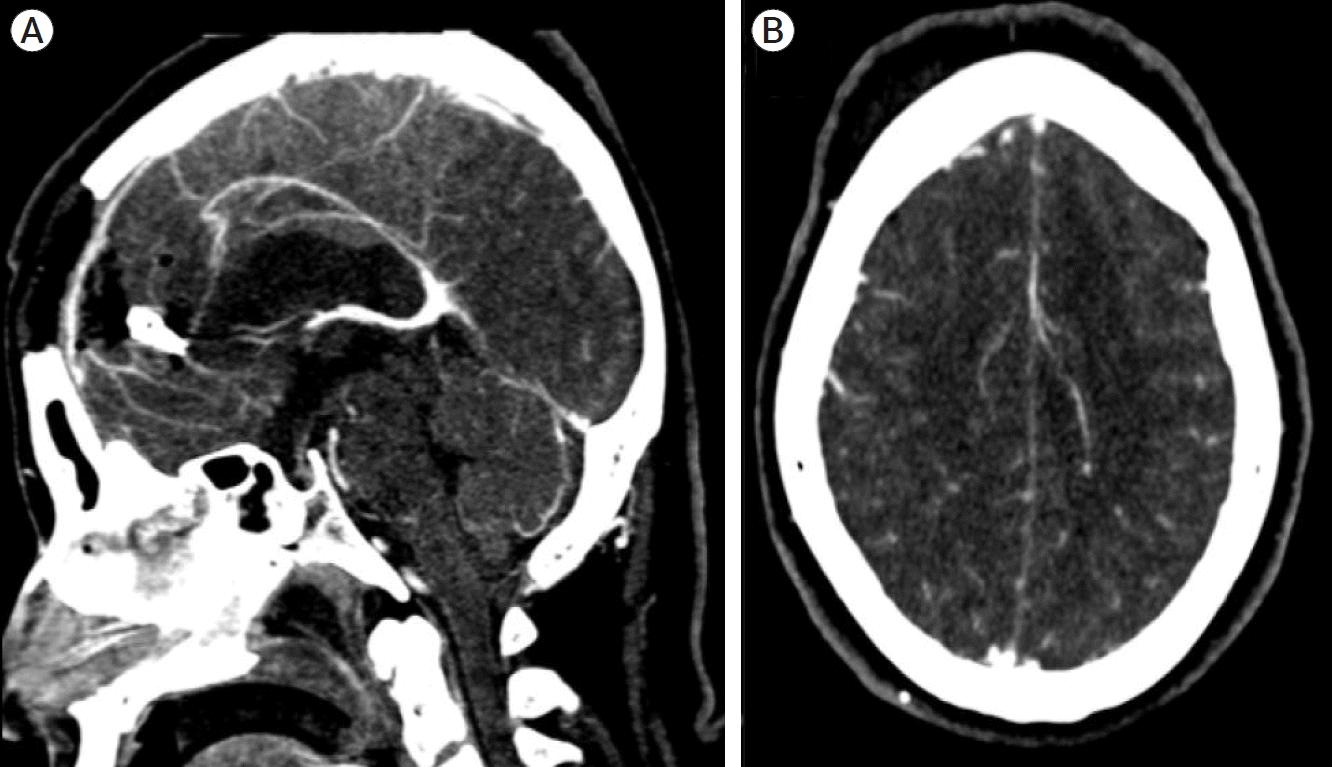

We describe the case of a 48-year-old female with a previous history of hypertension who was admitted to our emergency room due to generalized seizures. Neurological examination revealed a Glasgow coma scale of 11 (E3, V2, M6), a right central facial palsy, and a 3/5 right hemiparesis. A CT scan revealed a Fisher IV subarachnoid hemorrhage, an aneurysmatic lesion in the left DACA, and an associated right frontal intraparenchymal hematoma. Computed tomography angiography (CTA) and 3D reconstructions were performed to visualize the aneurysm’s dome projection and identify the related arteries (Fig. 1).

Fig. 1.

(A) Axial CTA showing a saccular aneurysm in the distal anterior cerebral artery. (B) 3D-reconstruction of the coronal CTA with evidence of a saccular aneurysm with a superior dome projection between callosomarginal and pericallosal arteries. CTA, computed tomography angiography